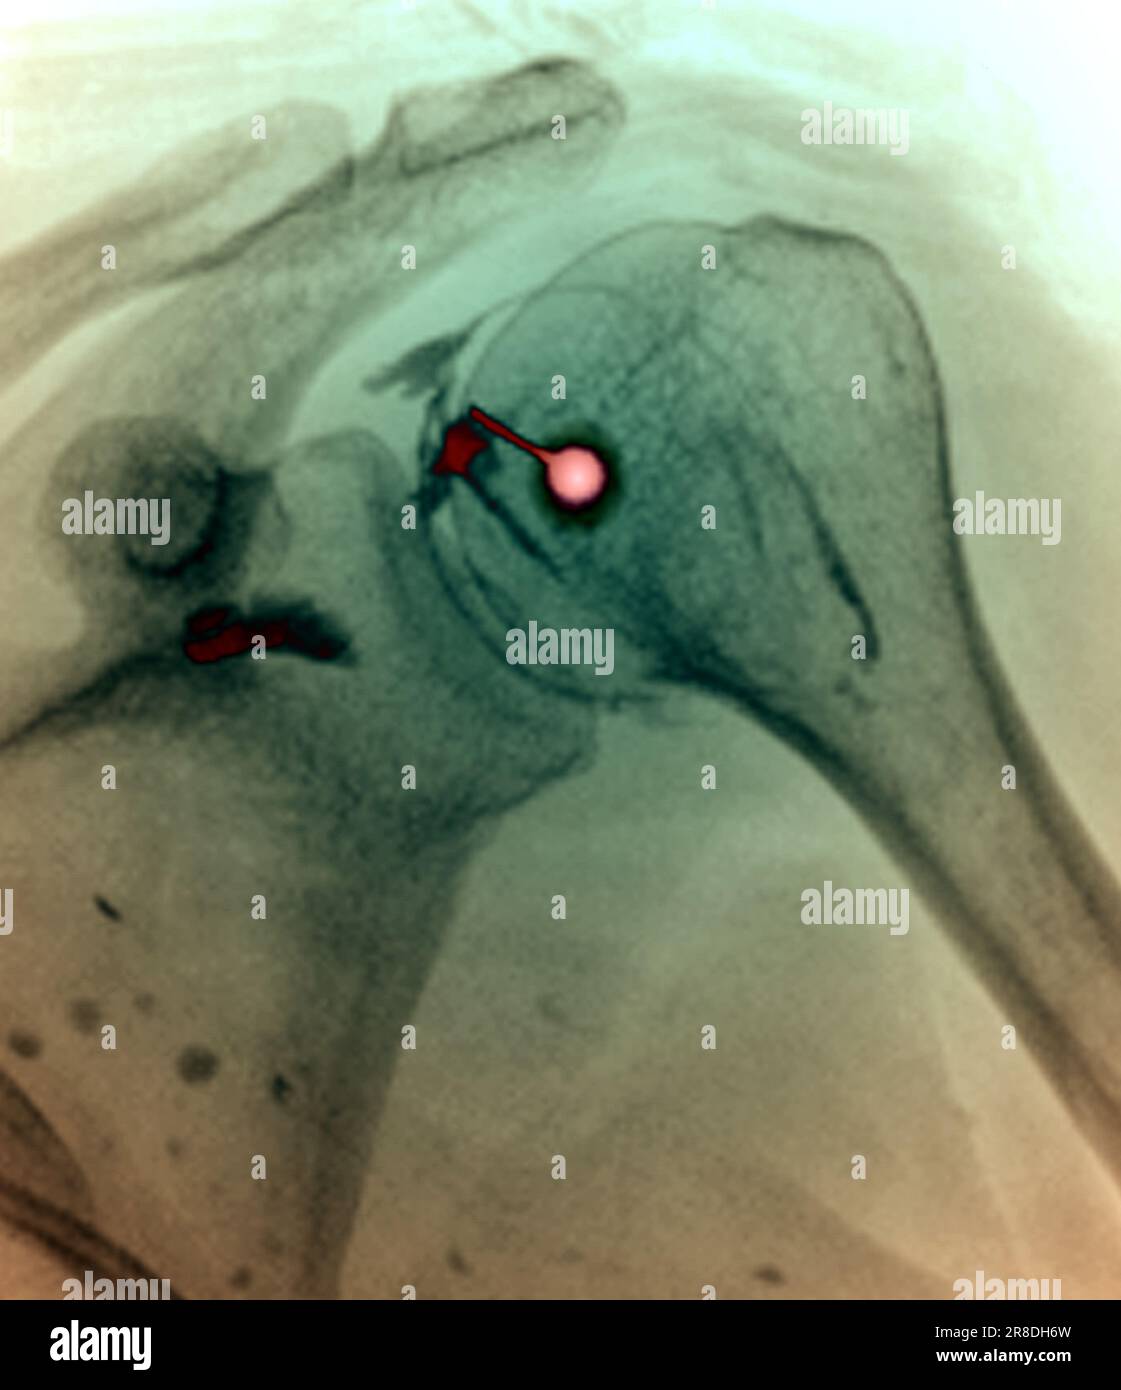

From www.alamy.com

Coloured Xray of a corticosteroid drug being injected into the shoulder of a 51 year old male Adhesive Capsulitis Frozen Shoulder X Ray Frozen shoulder, also called adhesive capsulitis, is a condition involving pain and stiffness in your shoulder joint. The diagnosis is commonly made through a combination of clinical history and physical examination findings, but early signs of. Adhesive capsulitis, also known as “frozen shoulder,” is a common shoulder condition characterized by pain and decreased range of motion, especially in external rotation.. Adhesive Capsulitis Frozen Shoulder X Ray.